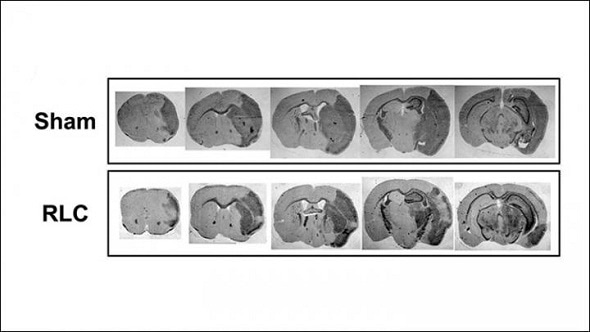

Sunghee Cho and colleagues at Burke Neurological Institute treated mice that experienced a stroke with remote ischemic limb conditioning and tested the monocyte levels in their blood. The research team found that the ratio of inflammatory to non-inflammatory monocytes circulating in the blood increased, resulting in more available inflammatory cells.

Surprisingly, the increase in circulating inflammatory cells was associated with reduced brain tissue damage and swelling and improved motor function. The symptoms improved for both moderate and severe strokes, indicating the potential for wide application as a stroke treatment.